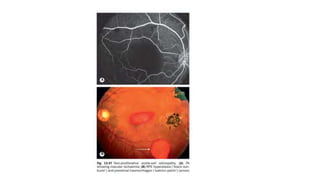

Cystoid Macular Edema

• Cystoid macular edema (CME) is characterized by intraretinal edema

contained in honeycomb-like cystoid spaces.

• The source of the edema is abnormal perifoveal retinal capillary

permeability

• FA shows multiple small focal leaks and late pooling of the dye in

extracellular cystoid spaces.

• OCT shows diffuse retinal thickening with cystoid areas that are more

prominent in the inner nuclear and outer plexiform layers.

• A non reflective cavity that is consistent with subretinal fluid

accumulation is present beneath the neurosensory retina.

• Pooling classically forms a “flower petal.